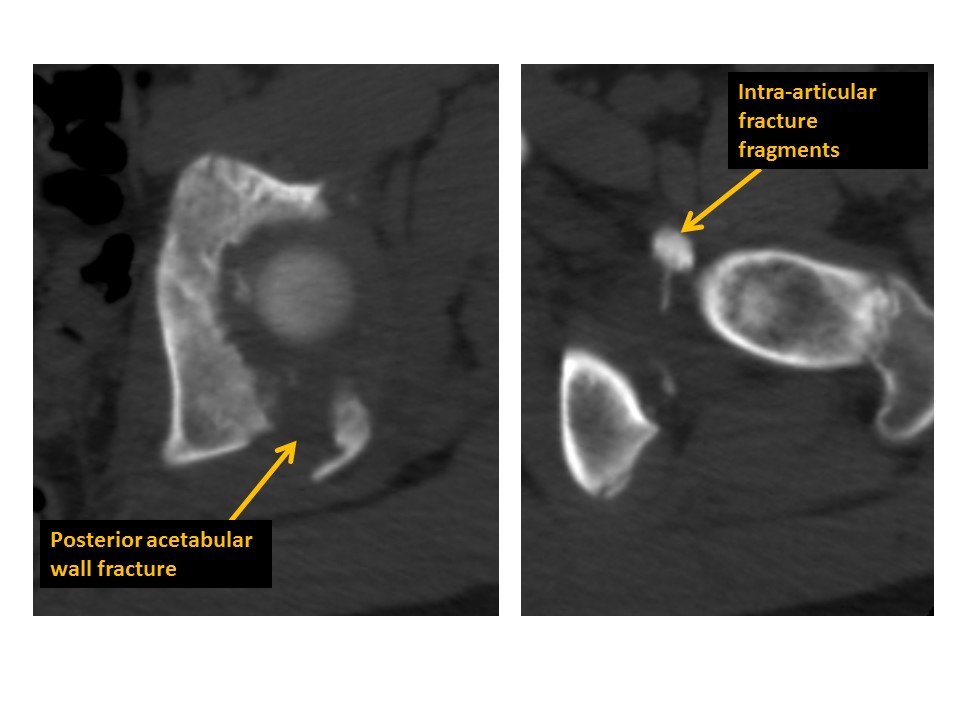

Acetabular fractures are present. [Yes/No]

There are intra-articular bodies within the hip joints. [Yes/No]